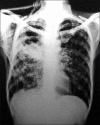

Subcutaneous emphysema in cavitary pulmonary tuberculosis without pneumothorax or pneumomediastinum

Extra-alveolar air in the form of subcutaneous tissue emphysema is observed in a variety of clinical settings. Spontaneous subcutaneous emphysema in the absence of pneumothorax or pneumomediastinum is very rare. We report a case of spontaneous subcutaneous emphysema secondary to cavitary pulmonary tuberculosis in the absence of pneumothorax or pneumomediastinum.